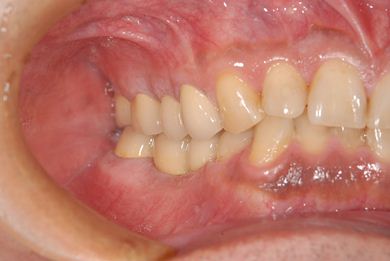

インプラントの症例写真 IMPLANT

インプラント治療+セラミック治療+歯肉歯槽骨整形術

| 主訴 | 悪いところの治療と、歯をきれいにしたい。 | ||||||||||||||||||||||||||||||||

| 治療方針 | 右下奥、保存不能な歯を抜歯し、インプラント治療にて、機能的・審美的回復を行う。 | ||||||||||||||||||||||||||||||||